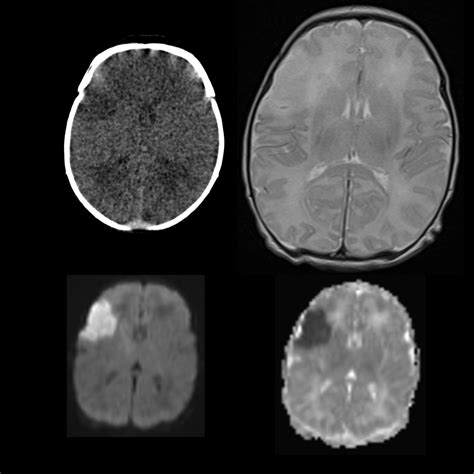

Types of CT Scans Used in Ischemic Stroke Diagnosis

Several types of CT scans can be used to diagnose ischemic stroke, each providing different levels of detail and information:

• Non-contrast CT (NCCT): This is the most basic type of CT scan and is often the first test performed. It provides a clear view of the brain structures and can detect early signs of ischemia, such as the “dense artery sign,” which indicates a blood clot.

• CT Angiography (CTA): This type of scan uses contrast dye to visualize the blood vessels in the brain. It can identify the location and extent of a blood clot and assess the condition of the blood vessels.

• CT Perfusion (CTP): This scan measures blood flow to different areas of the brain. It can help determine the extent of brain tissue that is at risk of dying (the penumbra) and guide decisions about thrombolytic therapy.

In some cases, a combination of these scans may be used to provide a comprehensive assessment of the stroke.